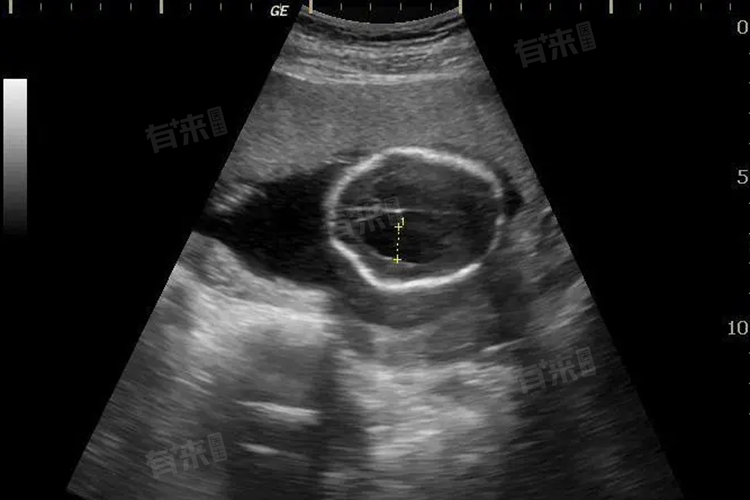

- 在技术应用上,二维超声是最基础的检查方式,通过超声波形成黑白断面图像,医生凭借经验和专业知识,从不同切面观察胎儿结构,是大排畸诊断的重要依据。三维超声则是在二维基础上,通过计算机技术重建胎儿立体静态图像。四维超声在三维基础上加入时间维度,可动态展示胎儿活动。虽然四维图像更生动,但二维超声对细节的精准判断,在大排畸中仍起着不可替代的作用。

临床实践中,不同医院开展大排畸检查的方式存在差异。有的医院使用二维超声结合彩色多普勒血流显像完成大排畸,专注于胎儿结构的细节观察和血流情况分析;部分医院会采用四维超声进行大排畸,它能让孕妇更直观地看到胎儿模样,但检查的核心依然是排查胎儿结构畸形。无论使用哪种技术,大排畸的关键都在于准确诊断胎儿是否健康。